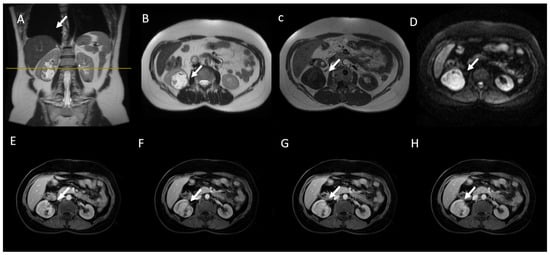

6. MRI Assessment

6.1. T2W Imaging

6.2. CS (IP D OP) Imaging

6.3. Diffusion-Weighted Imaging

6.4. Gadolinium-Enhanced Sequences

6.5. MRI in Bosniak Classification